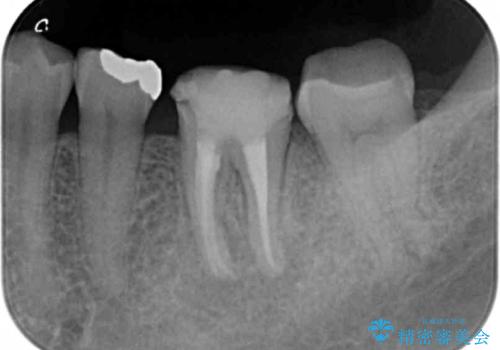

- 銀歯の部分で噛むと痛い、痛みが増している、と治療を希望され来院されました。

X線写真より根の先に病変が認められたため、根管治療を行ったのちジルコニアクラウンによる咬合機能回復治療を計画します。